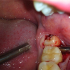

Удаление нижнего зуба мудрости

Сразу следует сказать, что подобные зубы удаляют далеко не в каждом хирургическом кабинете, поскольку от хирурга требуется очень высокая квалификация. Ведь никому не известно, что его ожидает, и с чем он может столкнуться в процессе выполнения данного вмешательства. Прежде всего нужно знать алгоритм удаления зуба, как проводить саму операцию, чтобы избежать врачебных ошибок. Лучше всего, если производится полное иссечение костной ткани над зубом, а потом он рассверливается бормашиной, после этого производится его удалении по фрагментам. После этого производится зашивание раны, и пациенту даются строгие рекомендации как себя вести. Не рекомендуется есть на сторону удаления, (правда это и невозможно будет), полоскать рот, - только на третий день можно очень плавно перекатывать воду во рту. Возможно появление сильных болей после операции, в таких случаях назначаются болеутоляющие средства, например препараты нимесулида.